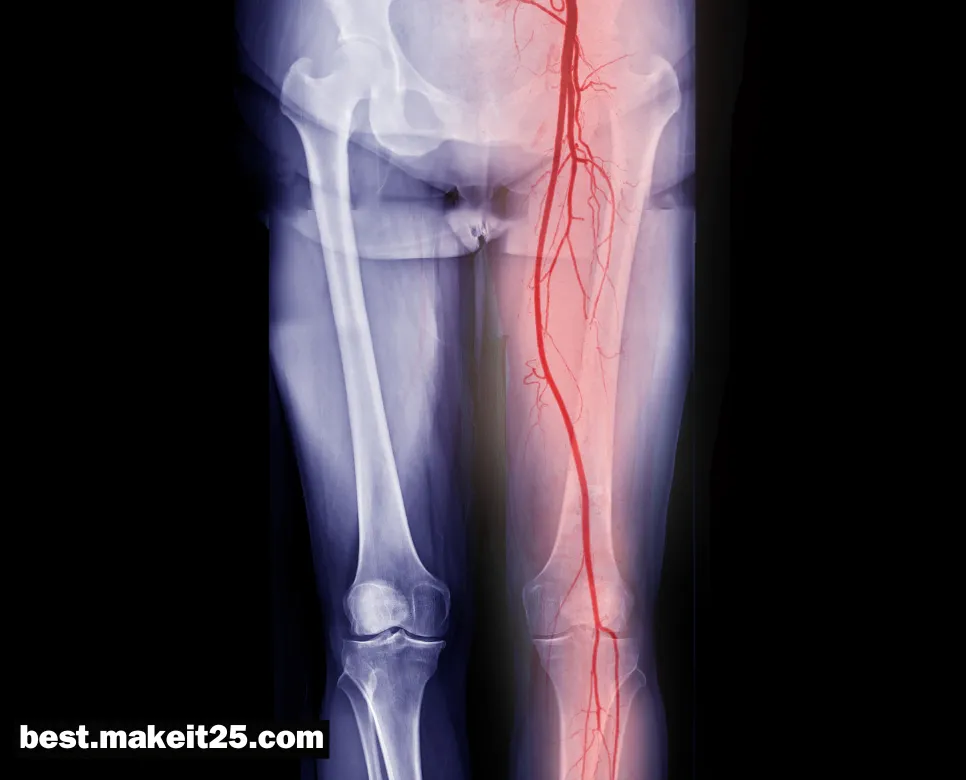

SFA(표재 대퇴동맥)

SFA는 의학 용어로 Superficial Femoral Artery의 약자이며, 한글로는 ‘표재 대퇴동맥’을 의미합니다. 표재 대퇴동맥은 대퇴동맥의 일부로, 서혜인대 아래에서 슬와동맥으로 이어지는 동맥입니다. 하지의 주요 혈액 공급 경로 중 하나로, 하지 말초동맥질환의 호발 부위이기도 합니다.

- 위치: 대퇴동맥에서 분지되어 대퇴부 전면을 따라 내려가다 슬와동맥으로 이어집니다.

- 진단: 이학적 검사, 발목상완지수(ABI) 측정, 도플러 초음파, 혈관조영술 등을 통해 진단합니다.

- 중재적 시술: 경피적 혈관성형술, 스텐트 삽입술 등을 통해 혈류를 개선시킬 수 있습니다.

- 수술적 치료: 동맥 우회로조성술, 혈전내막절제술 등의 수술적 치료를 고려할 수 있습니다.

결론적으로, SFA는 주로 표재 대퇴동맥을 지칭하는 의학 용어로, 하지 말초동맥질환의 호발 부위입니다. 폐쇄성 동맥경화증, 혈전증, 동맥류 등의 질환이 발생할 수 있으며, 진단을 위해 다양한 검사를 시행하고, 내과적 치료, 중재적 시술, 수술적 치료 등의 방법으로 접근합니다. 또한 SFA는 포화 지방산을 의미하기도 합니다.